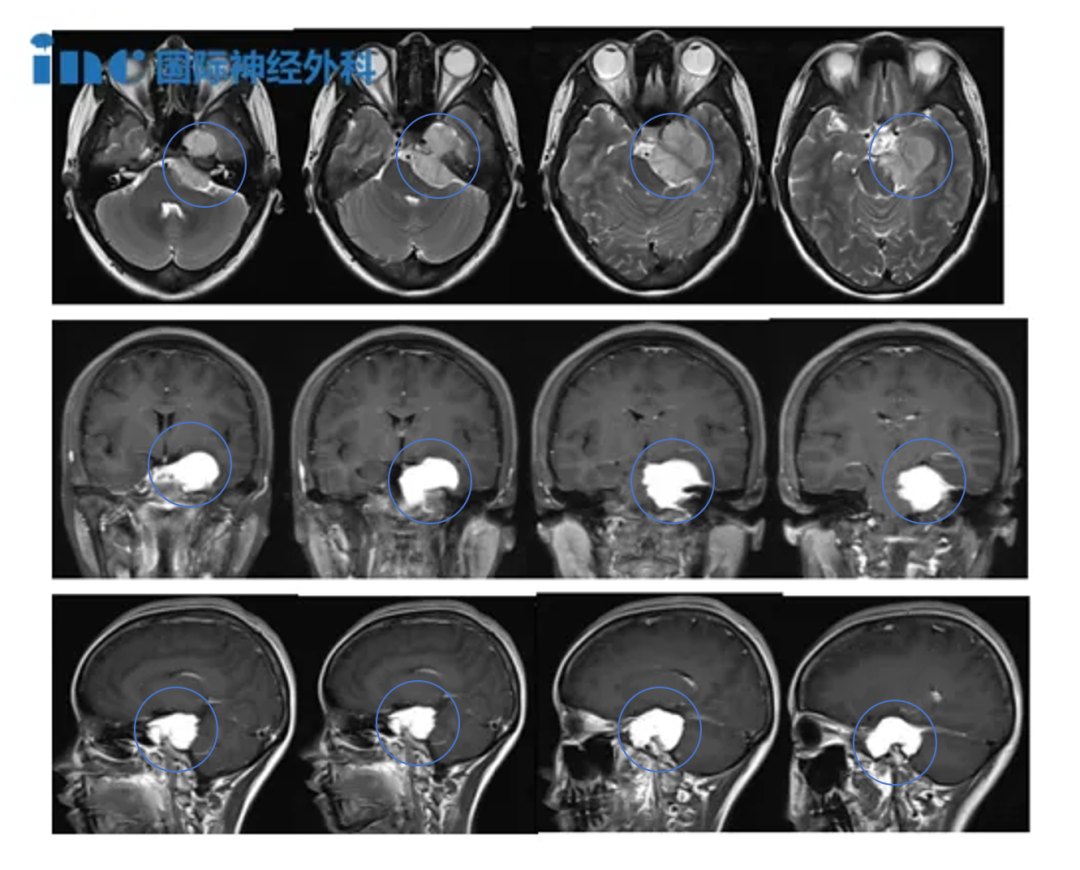

然而事实是,她所对抗的是一个体积约达4.5厘米的岩斜区脑膜瘤。该肿瘤已对脑干及左颞叶形成严重压迫,甚至在术前短短一个月内,将其左眼视力侵蚀至仅剩0.1。如今,肿瘤已被成功切除,其术后恢复进程更是令人感到惊喜——

但当我把这个消息告知家人后,所有人的反应出奇地一致:“长在脑子里的东西就是定时炸弹,必须处理!”他们建议我立即前往大型医院,寻找专家进行诊治。于是我开始挂号、咨询,一位、两位、三位……直到此时我才了解到,肿瘤已经长得很大了(45x38x32mm)。所有接诊的神经外科专家都得出了相同的结论:肿瘤体积巨大,位置关键,建议尽快进行手术。

▼岩斜区脑膜瘤,随着肿瘤体积增大及伴随脑干水肿发生几率增加,手术难度呈现逐渐上升趋势。